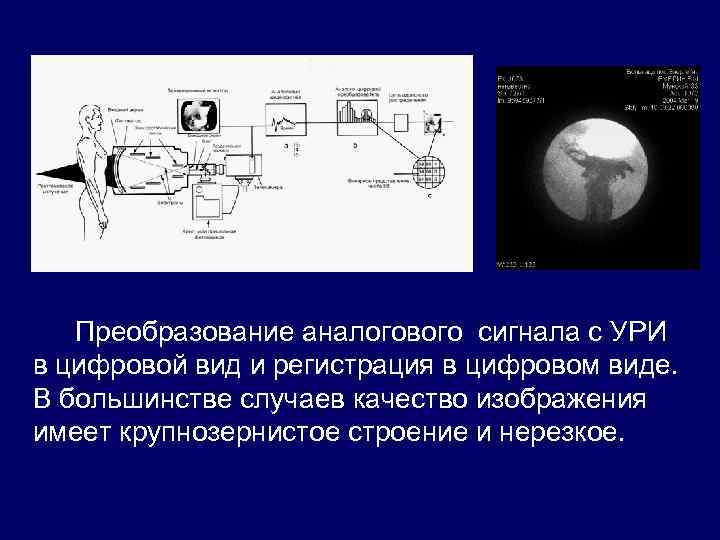

Преобразование аналогового сигнала с УРИ в цифровой вид и регистрация в цифровом виде. В большинстве случаев качество изображения имеет крупнозернистое строение и нерезкое.